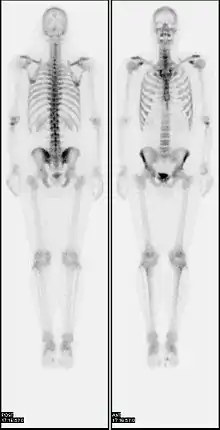

جرقهنگاری استخوان

جرقه نگاری استخوان یک تکنیک پزشکی هسته ای تصویربرداری از استخوان است. که میتواند به تشخیص برخی از شرایط استخوانی، از جمله سرطان استخوان یا متاستاز، محل التهاب استخوان و شکستگی (که ممکن است در تصاویر X-ray سنتی دیده نشود) و عفونت استخوان کمک کند.[1]

در روش معمول اسکن استخوان، به بیمار یک ماده رادیواکتیو تزریق میشود (معمولاً به ورید در دست یا، گاهی اوقات پا) مثلا ۷۴۰ بکرل از تکنسیوم 99m-MDP و سپس با یک دوربین گاما اسکن انجام می شود که میتواند به دو گونه باشد.نوع پلانار یا مسطح که تصاویر قدامی و خلفی میدهد و یا بصورت تابش تک فوتون توموگرافی کامپیوتری (SPECT) که در طی ان دوربین گاما 360 درجه بدور بدن چرخیده و تصاویر را بصورت سطح مقطعی یا سکشنال (sectional) ارایه میدهد.[17][18] به منظور مشاهده ضایعات کوچک، تکنیک تصویربرداری SPECT ممکن است بر اسکن پلانار یا مسطح ترجیح داده شود.[19] در یک پروتکل تک فاز (تصویربرداری اسکلت به تنهایی)، که در ابتدا اسوتوبلاستها را برجسته میکند، تصاویر معمولاً ۲ تا ۵ ساعت پس از تزریق به دست میآیند (پس از چهار ساعت ۵۰ تا ۶۰٪ فعالیت به استخوانها ثابت میشود).[17][18][20] پروتکل دو یا سه فاز از اسکنهای اضافی در نقاط مختلف بعد از تزریق برای دریافت اطلاعات تشخیصی اضافی استفاده میکند. یک پویا (یعنی فریمهای چندگانه) بلافاصله بعد از تزریق، اطلاعات مربوط به پرفیوژن را ثبت میکند.[20][21] فاز دوم "تصویر خون خون" پس از پرفیوژن (اگر در یک تکنیک سه مرحله انجام شود) میتواند به تشخیص بیماریهای التهابی یا مشکلات خون کمک کند.[22] یک دوز مؤثر در طول اسکن استخوان ۶٫۳ میلی ثانیه (mSv) است.[23]